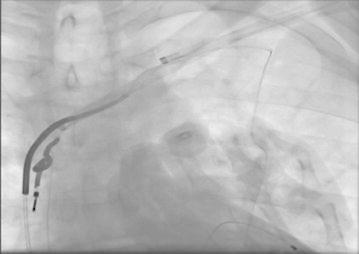

Lead extraction procedures were performed in cardiac catheterisation laboratory under local anesthesia and conscious sedation with non-invasive blood pressure monitorisation. Although most experts prefer to use invasive blood pressure monitorisation during the procedure due to technical difficulties in our laboratory we used non-invasive monitorisation. We increased the frequency of blood pressure measurements at the critical stages of the procedure; during advancement of the system at the subclavian vein and superior vena cava angle and while performing countertraction at the distal tip of implanted electrodes. There are successful reports of non-invasive monitorisaton during procedure (Oto et al. 2011, 2012); but it is better to have invasive blood pressure monitorisation when available. Temporary pacemakers were implanted from femoral vein before procedure in pacemaker dependent patients. Pacemaker pocket region was explored using a sterile method and pacemaker generator was explanted. The leads were explored and separated from surrounding fibrous tissues, sleeves and the capsule using blunt dissection while protecting lead’s lumen and integrity. After dissection of the lead from fibrous tissue up to subclavian vein puncture site; patency of lead’s lumen was checked by a standard stylet. If an active fixation lead was present, it was unscrewed from the endocardium. If the lead could not be explanted by gentle simple traction then special locking sytlet was exchanged with standard sytlet. This locking stylet was advanced towards the distal endocardial implantation site to fix the lead from the distal end. If the lumen’s integrity was damaged or locking stylets could not be advanced to the distal portion of the electrodes, a bulldog system was used for the fixation of lead in 11 (26.8 %) of our patients. After the fixation of lead, mechanical dilator sheath was advanced over lead and locking stylet complex. The distal blades of mechanical dilator sheath cuts the fibrotic adhesions around the lead and the outer polymer sheath protects vascular structures. Extremely adhered leads could be separated by using two dilators and an example of such condition which occured in two of our patients is shown in Fig. 1. It was imperative to stay co-axial to the lead’s plane at all times for protecting lead’s integrity during procedure. When distal implantation site was reached, instead of dilator’s metal distal end, outer polymer sheath was advanced to perform countertraction. By countertraction the distal tip of lead was liberated from endocardium without causing avulsion. Then lead was pulled back into outer polymer sheath without leaving any foreign material in vascular system. If any lead remnants remained in vascular spaces they are removed by using snares from femoral route. We used 2 types of snares Needle’s Eye Snare (Cook Vascular, Leechburg PA USA) in one patient and Multisnare (Multisnare, PFM, Köln, Germany) in four patients. In pacemaker dependent patients who have undergone lead extraction procedure because of infection, new battery and lead implantation was performed at the contralateral site after having negative blood cultures for 72 h; which were obtained in 24 h of lead extraction procedure. In other patients the new battery and leads were implanted at the same or another session at the contralateral site. After the procedure cardiac rhythm, hemodynamic status of patient were monitored closely in the intensive care unit regarding development of bleeding complications, pericardial tamponade, arrythmia problems. A lead extracted in our hospital is shown in Fig. 2.

Fig. 1.

Combined use of two mechanical dilator sheaths for separation of extremely adhered leads